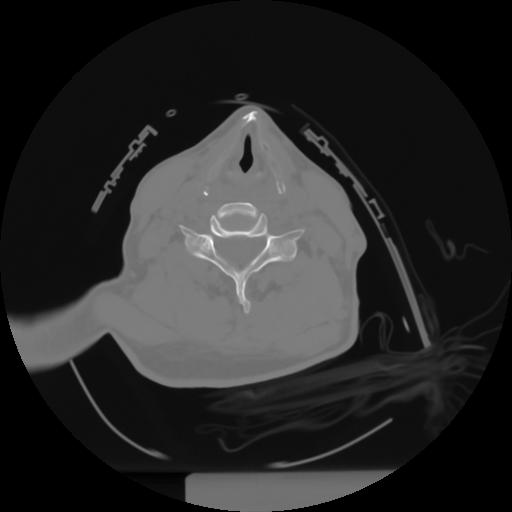

10 P.BLANDAS,,Axial,2.0,P.BLANDAS,,